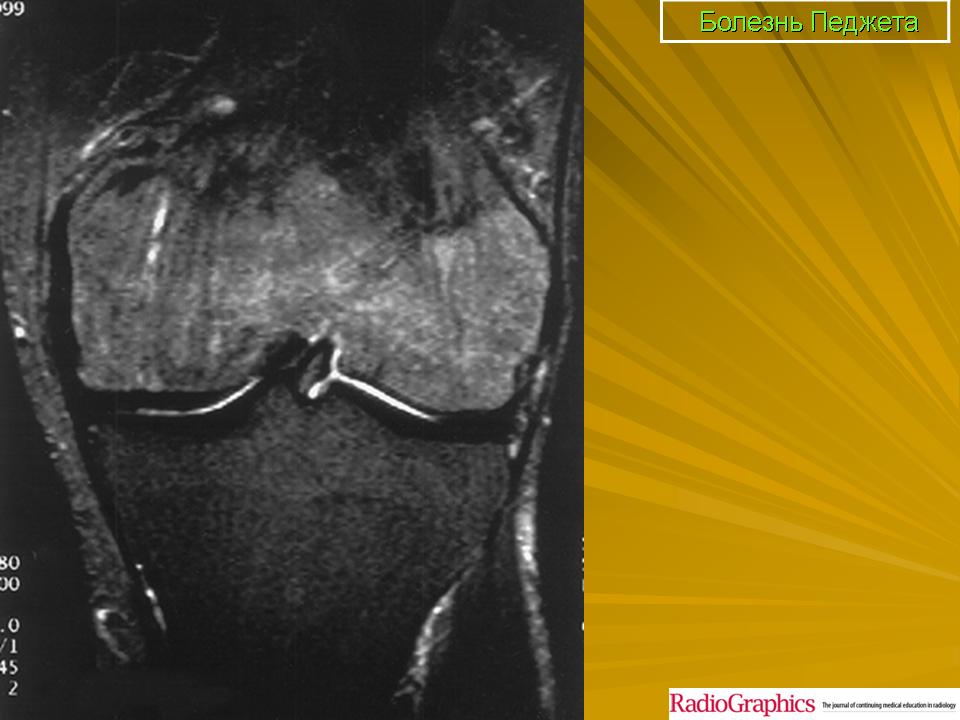

Педжета болезнь (J. Paget англ. хирург, 1814-1899; синоним: деформирующий остоз, деформирующий остит, деформирующая остеодистрофия) - заболевание скелета, при котором наблюдается поражение одной или нескольких костей в результате патологической перестройки костной ткани.

Принято различать три фазы развития П. б.: очаговая интенсивная резорбция кости (остеолитическая, или деструктивная, фаза), смешанная фаза, когда наряду с рассасыванием кости идут процессы новообразования ее, и остеобластическая, или склеротическая, фаза с образованием типичных мозаичных структур.